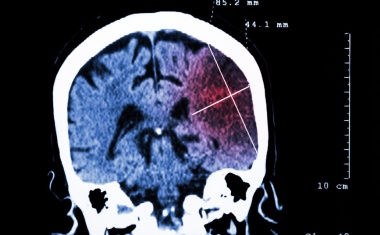

Was passiert bei einem epileptischen Anfall im Gehirn? Was nach einer Lähmung durch Schlaganfall? Was im Kopf von Parkinson-Erkrankten?